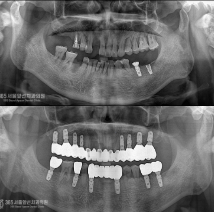

전체임플란트, 발치와 동시에 전체 임플란트 치료를 시행한 환자분

안녕하세요. 주안역치과 365서울앞선치과의원입니다.오늘은 발치와 동시에 전체 임플란트 수술을 한 원데이..